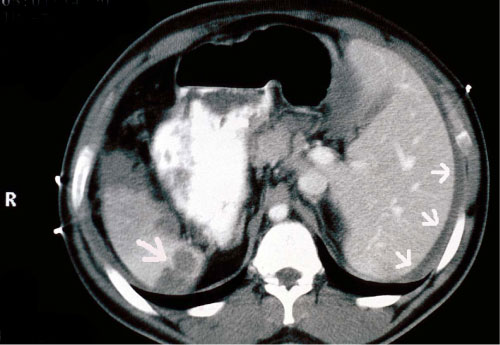

His chest radiograph demonstrated r right sided cardiac apex. His focused assessment with sonography in trauma (FAST) examination revealed the presence of fluid in Morison's pouch in the left upper quadrant (Figure 2), contusion over the spleen in the right upper side (Figure 3), but no free fluid in the pelvis or pericardial fluid. His computed tomography scan (CT) demonstrated fluid around the liver without solid liver organ injury and multiple splenic contusions (Figure 4).

Figure 4: CT scan show perihepatic fluid (arrows on the right) and splenic contusion (arrow on the left). View Figure 4